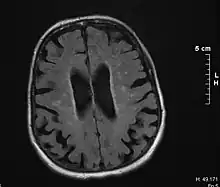

Binswanger's disease can usually be diagnosed with a CT scan, magnetic resonance imaging, and proton magnetic resonance spectrography in addition to clinical examination. Indications include infarctions, lesions, or loss of intensity of central white matter and enlargement of ventricles, and leukoaraiosis. A mini–mental state examination has been created to quickly assess cognitive impairment and serves as a screening test for dementia across different cultures.[13]

Leukoaraiosis refers to the imaging finding of white matter changes that are common in Binswanger disease. However, leukoaraiosis can be found in many different diseases and even in normal patients, especially in people older than 65 years of age.[5]

There is controversy whether leukoaraiosis and mental deterioration actually have a cause and effect relationship. Research has shown that different types of leukoaraiosis can affect the brain differently, and that proton magnetic resonance spectroscopy would be able to distinguish the different types more effectively and better diagnose and treat the issue.[9] Because of this information, white matter changes indicated by magnetic resonance imaging or computerized tomography cannot alone diagnose Binswanger disease, but can aid to a bigger picture in the diagnostic process. There are many diseases similar to Binswanger's disease including CADASIL syndrome and Alzheimer's disease, which makes this specific type of white matter damage hard to diagnose.[5] Binswanger disease may be diagnosed by a team of experts including a neurologist and psychiatrist to rule out other psychological or neurological problems.[3] Because doctors must successfully detect enough white matter alterations to accompany dementia as well as an appropriate level of dementia, two separate technological systems are needed in the diagnosing process.

Much of the major research today is done on finding better and more efficient ways to diagnose this disease. Many researchers have divided the magnetic resonance imaging of the brain into different sections or quadrants. A score is given to each section depending on how severe the white matter atrophy or leukoaraiosis is. Research has shown that the higher these scores, the more of a decrease in processing speed, executive functions, and motor learning tasks.[14][15] Other researchers have begun using computers to calculate the percentage of white matter atrophy by counting the hyper-intense pixels of the magnetic resonance images. These and similar reports show a correlation between the amount of white matter alterations and the decline of psychomotor functions, reduced performance on attention and executive control.[16][17] One type of technology is called susceptibility weighted imaging (SWI) which is a magnetic resonance technique which has an unusually high degree of sensitivity and can better detect white matter alterations.[18]